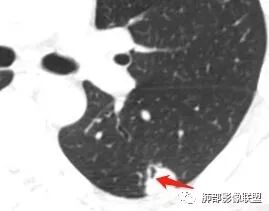

支气管树爬行征这个观点是袁怀平老师提出来的。当时提出了一个观点,就是说支气管是通畅的。

现在就是支气管树爬行征的认定问题,就是关于支气管通与不通?如果堵塞,在哪个区域堵塞?

支气管树爬行征就是肉芽肿性病变,不过它是沿着支气管周围间质往里面走的。我们以前认定支气管要通畅的,但是我们读了隐球菌发现,包括肺炎性肺癌,你就发现外围的病变往内带进展,可以支气管堵塞,例如隐球菌有个特点非常明显的,一个大片状影,支气管在中近端堵塞。我们反推过来,结核也可以这样变化;支气管爬行征原来是要求支气管通畅,改良为支气管可以通畅,也可以在中间堵塞。

该如何判断支气管树爬行征,还需要大宗数据进行观察总结。

支气管树爬行征:肺内结核性肉芽肿的特征性CT征象之一